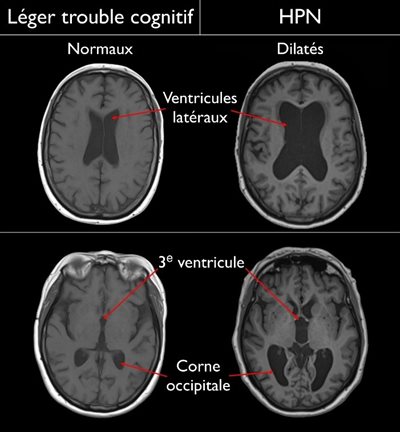

Touchant 3/200 personnes âgées de plus de 70 ans, l’hydrocéphalie à pression normale (HPN) est une affection neurologique entraînée par une accumulation excessive de liquide céphalo-rachidien (LCR) dans les ventricules du cerveau.

Puis, il est appuyé avec une imagerie par résonance magnétique (IRM), qui permet de voir précisément votre cerveau pour vérifier si les ventricules sont plus grands que la normale.

Image du cerveau montrant un état normal et un état avec trouble cognitif.